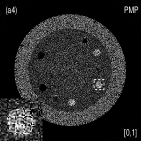

Fig. 4 shows the decomposed material images by the Direct Inversion, the PWLS-EP-LOOP and the PWLS-TNV- method. The left corners of the to the column of Fig. 4 show enlarged rods that are highlighted with white dashed boxes in decomposed material images. Table 2 summarizes the means and noise STDs of ROIs of decomposed basis material images. The volume fraction (VF) accuracies were , , and for the Direction Inversion, the PWLS-EP-LOOP and the PWLS-TNV- method, respectively. Compared with the Direct Inversion and the PWLS-EP-LOOP method, the proposed PWLS-TNV- method increases the VF accuracy by and respectively.

Table 3 summarizes the average electron densities of contrast rods and RMSE() of electron density for the three MMD methods. The RMSE() was , and for the Direct Inversion method, the PWLS-EP-LOOP method and the proposed PWLS-TNV- method, respectively. The proposed PWLS-TNV- method suppressed noise, decreases crosstalk and increased decomposition accuracy in the material images, while maintaining high image quality.